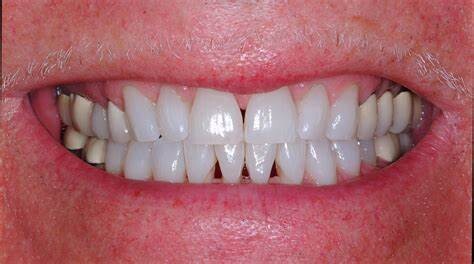

Have you lost gum from between your teeth? If you look at any magazine photo or advertisement you will see cosmetically beautiful smiles with uniform, straight teeth. The smiles you see in these magazines do not have gaps or spaces. If you have tiny triangles between two or more of your teeth, you may feel self conscious about their appearance.

Unfortunately, lost gum between teeth can indicate that the tissue is not as healthy and strong as it should be. Often, gum treatment is needed before cosmetic alterations can be made to fill these spaces. Good oral hygiene is important for your teeth and gums and patients are encouraged to improve how they brush and floss. Once your gums have been treated and are healthy, treatment for the dark spaces can be done. You can say goodbye to these black spaces in your smile through one of three treatment options.

Veneers:

Crafted from very thin pieces of ceramic, veneers act as a type of cover for your front teeth. They can camouflage a host of cosmetic issues in an otherwise healthy, functional dentition. Often old composite veneers are replaced with porcelain. Dental veneers are one of the best ways to improve the cosmetic appearance of teeth in a relatively short amount of time. It often takes just a couple of appointments to receive the veneers to camouflage the host of esthetic issues, including spaces between your teeth. However, due to their custom fabrication and design, ceramic veneers are pricier than other cosmetic treatments. Dental veneers last on average 15 to 20 years before needing replacement. Most clients who choose them feel that veneers are worth it.